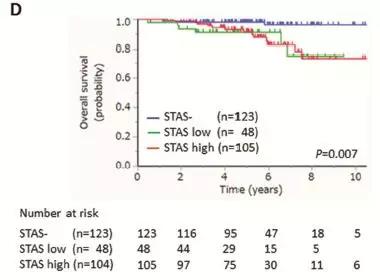

图表D,不同程度的STAS,5年肺癌相关的总体生存率明显下降